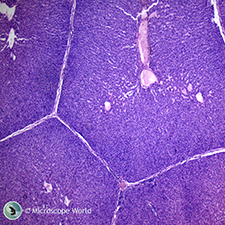

| Hydra with Bud | Kidney c.s. | |